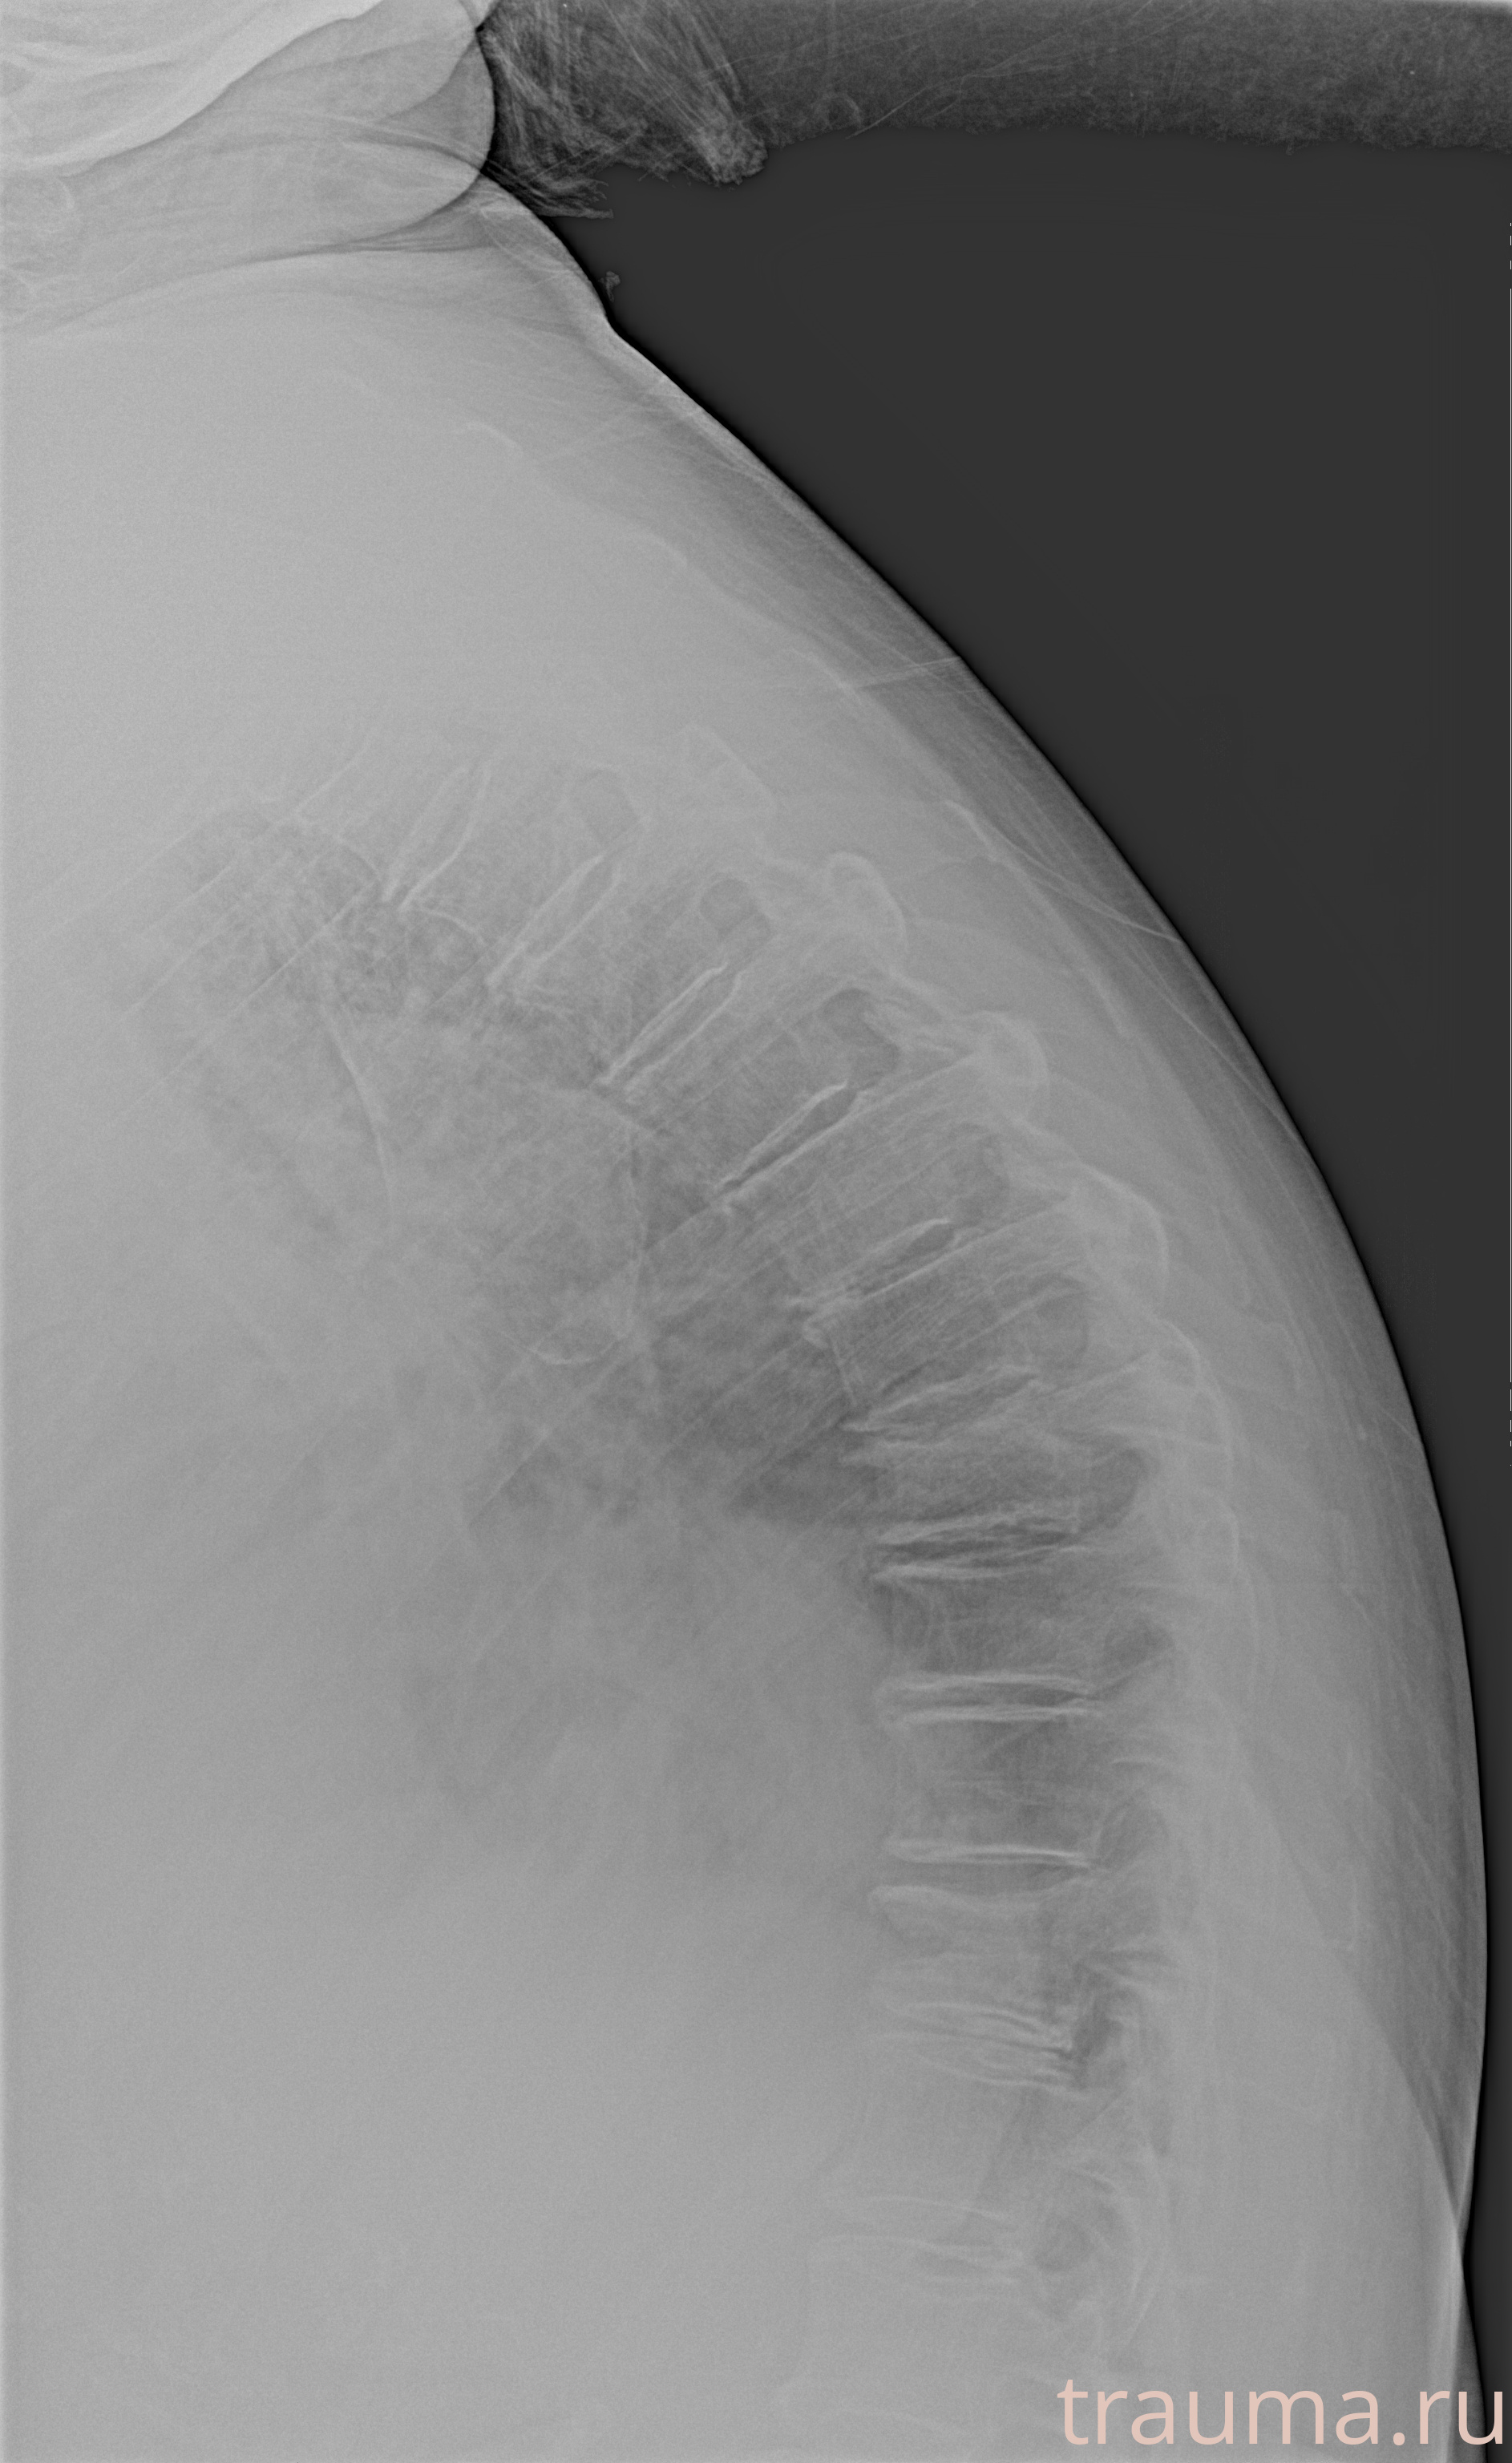

Рентген на дому: по вашему адресу приезжает врач-рентгенолог, травматолог-ортопед с мобильным рентгеновским аппаратом, проводит диагностику травмы или заболевания, делает необходимые рентгенограммы, дает рекомендации по дальнейшему лечению. Получить качественные снимки в домашних условиях возможно благодаря уникальной методике, разработанной МосРентген Центром для института  Склифосовского

при переломе шейки бедра и пневмонии от компании МосРентген Центр - партнера Института имени Склифосовского